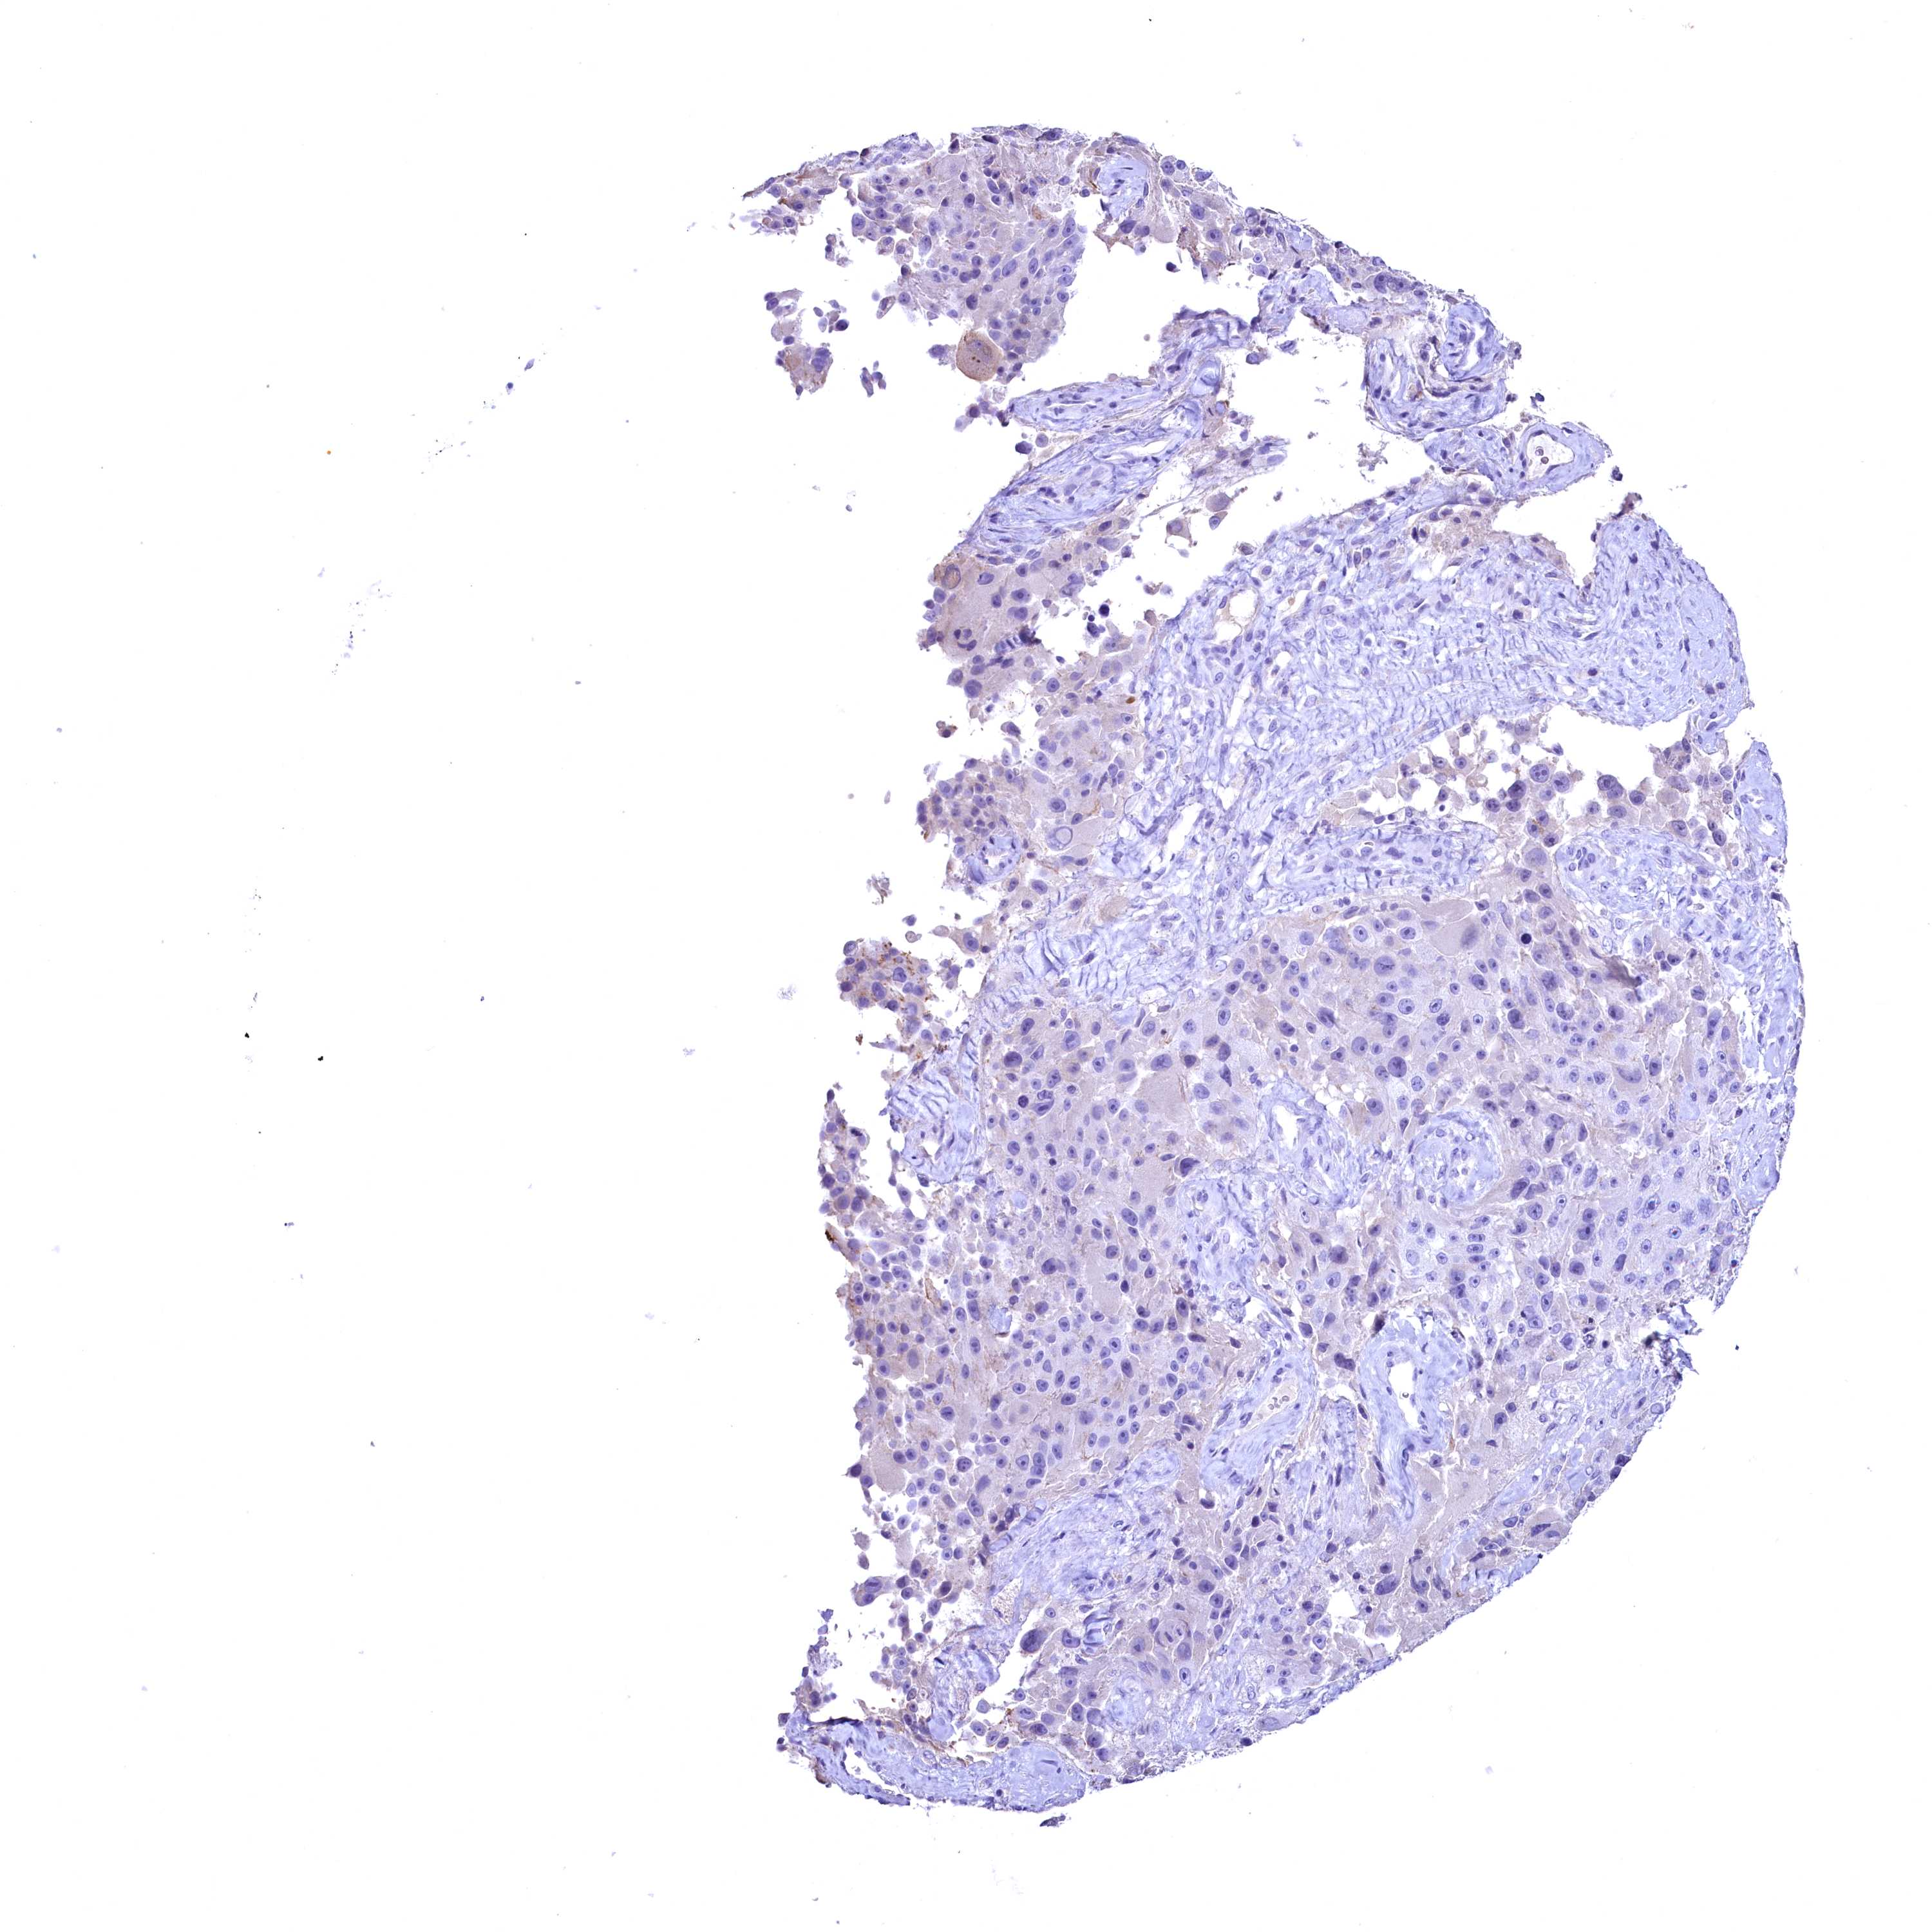

MELANOMA - Protein expressioni

A mouse-over function shows sample information and annotation data. Click on an image to view it in a full screen mode. Samples can be filtered based on level of antibody staining by selecting one or several of the following categories: high, medium, low and not detected. The assay and annotation is described here.

Antibody stainingi

Antibody staining in the annotated cell types in the current human tissue is reported as not detected, low, medium, or high, based on conventional immunohistochemistry profiling in selected tissues. This score is based on the combination of the staining intensity and fraction of stained cells.

Each image is clickable and will lead to virtual microscopy that enables deeper exploration of all samples and also displays staining intensity scores, fraction scores and subcellular localization as well as patient and tissue information for each sample.

Antibody HPA039208

Staining

Not detected

Negative

None

Malignant melanoma, NOS